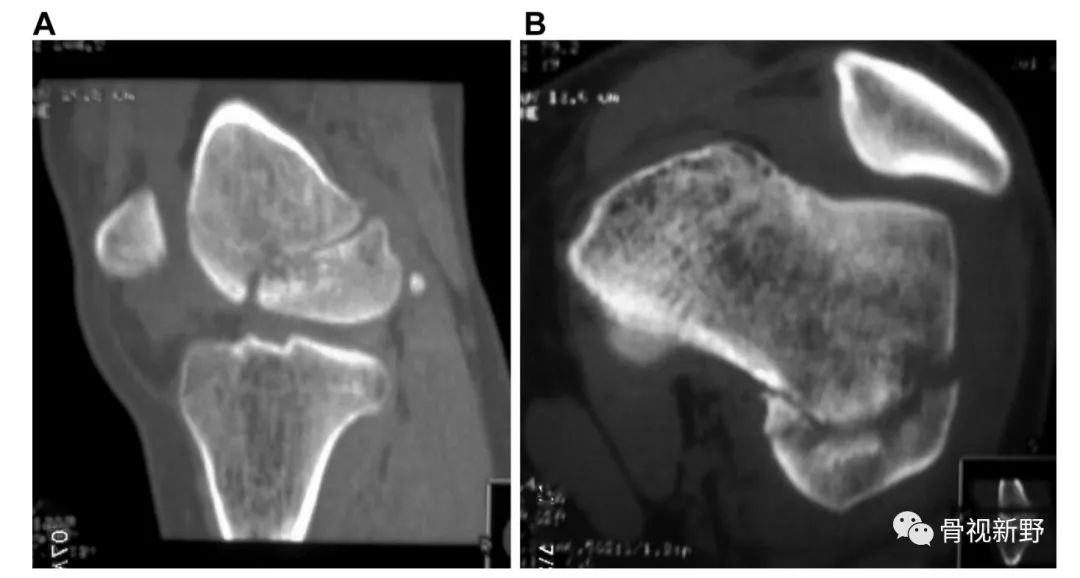

影像诊断:部分Hoffa骨折X线片不能提供明确的诊断,漏诊率较高。需要CT或MRI检查,并根据患者的病史、查体及影像学检查予以确诊。

部分Hoffa骨折普通X光片易漏诊

CT扫描在矢状位、轴位容易发现骨折及骨折线的走形方向